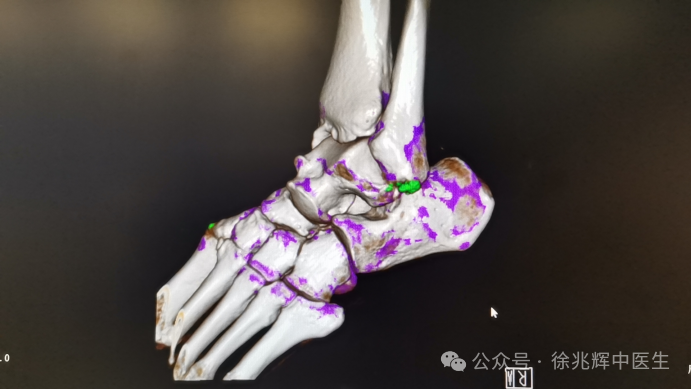

1. 双能量减影:自动分离尿酸结晶(呈现亮绿色)与钙化灶(显示为紫色);

2. 亚毫米级分辨率:可检测直径0.5mm的微小结晶,比传统CT敏感度提升40%;

3. 三维成像技术:立体展示结晶在滑膜、软骨甚至肌腱中的分布。

临床研究显示,双源CT诊断痛风的特异性达93%,甚至能早于症状出现前发现尿酸盐沉积,实现超早期干预。

2. 精准定位:识别第一跖趾关节、踝关节等痛风好发部位尿酸盐结晶的隐匿沉积;

3. 疗效监测:量化尿酸盐体积,动态评估降尿酸治疗的效果;

国际痛风诊疗指南已将双源CT发现尿酸盐结晶列为诊断痛风的金标准。建议高危人群(肥胖、酗酒、有家族史者)在出现关节肿痛时,优先选择双源CT检查。早期发现尿酸盐沉积,通过药物联合生活方式干预,可减少90%的痛风石形成风险。